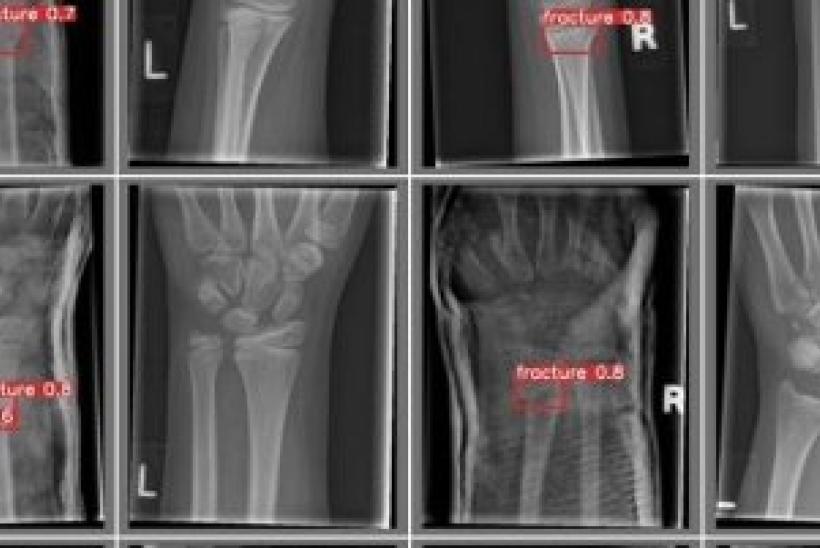

A team led by Professor Susan Shelmerdine, Consultant Radiologist at GOSH, put together the application in which they outlined their ambitions to develop a pioneering AI tool, to transform care for children with wrist fractures – the most commonly fractured bone in childhood.

This innovative system will detect and classify the type of fracture, align treatment recommendations with the latest evidence-based guidelines, and automatically draft radiology reports and referral letters for doctors and patients to speed up and enhance patient care.

Supported by AWS, GOSH will be using a range of x-rays from child wrist fractures to train and validate the tool, setting a new standard for digital innovation in child fracture management.